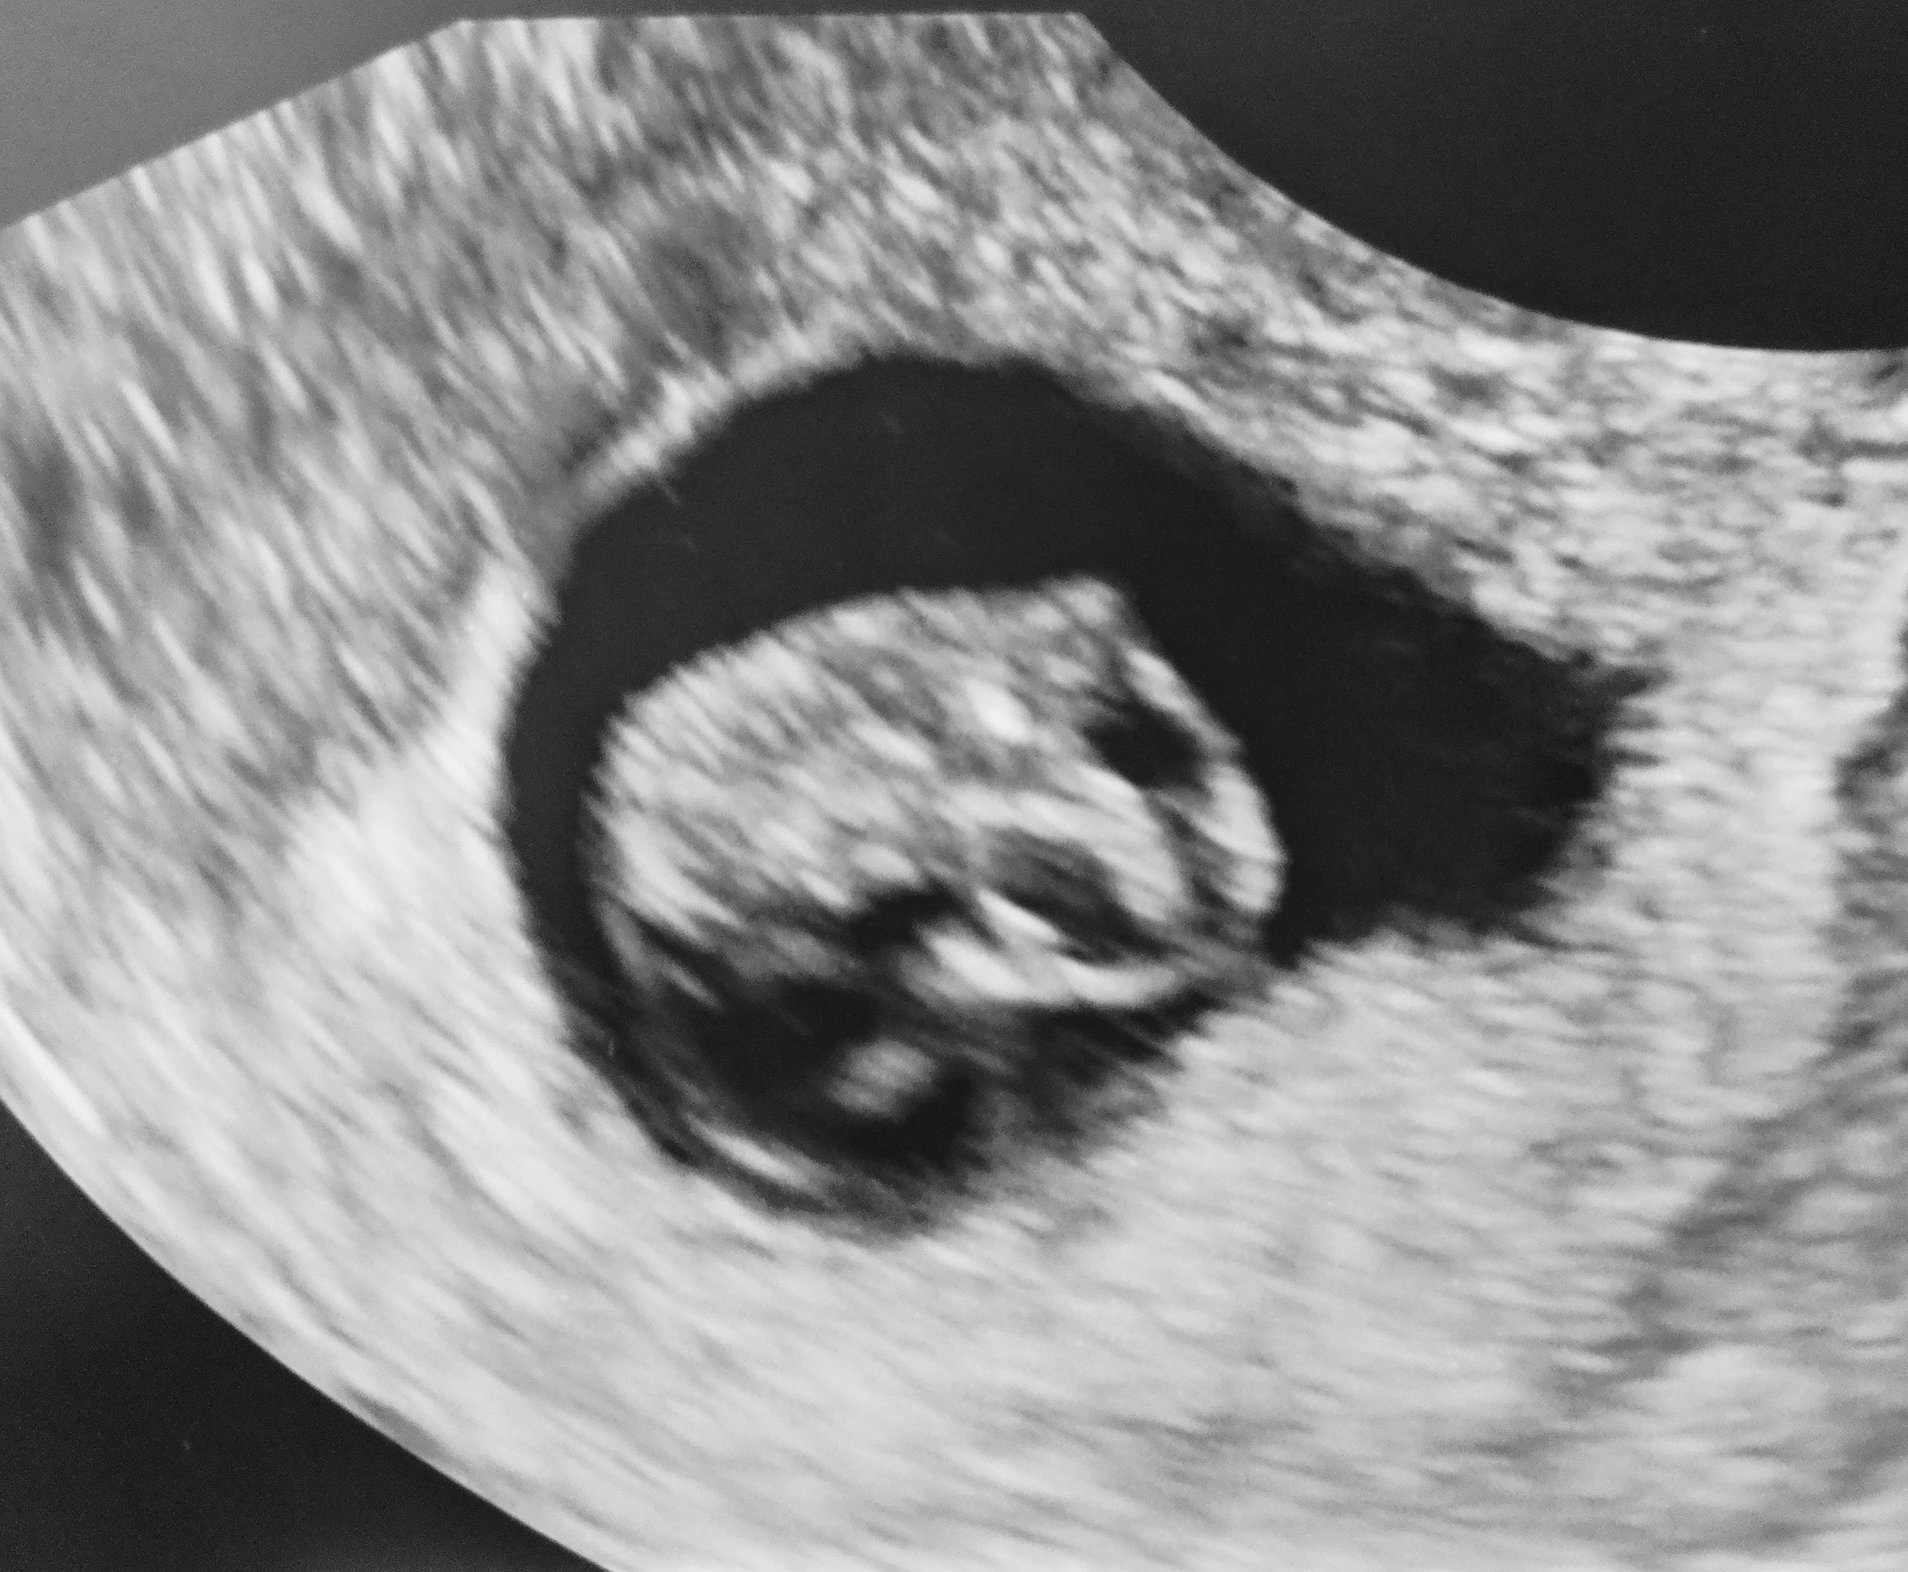

Had another ultrasound Sunday at the ER I was 9w2d and I had pain and bleeding. They found a hemorrhage but baby was doing good HR was 170 and the baby even looks like they’re smiling!